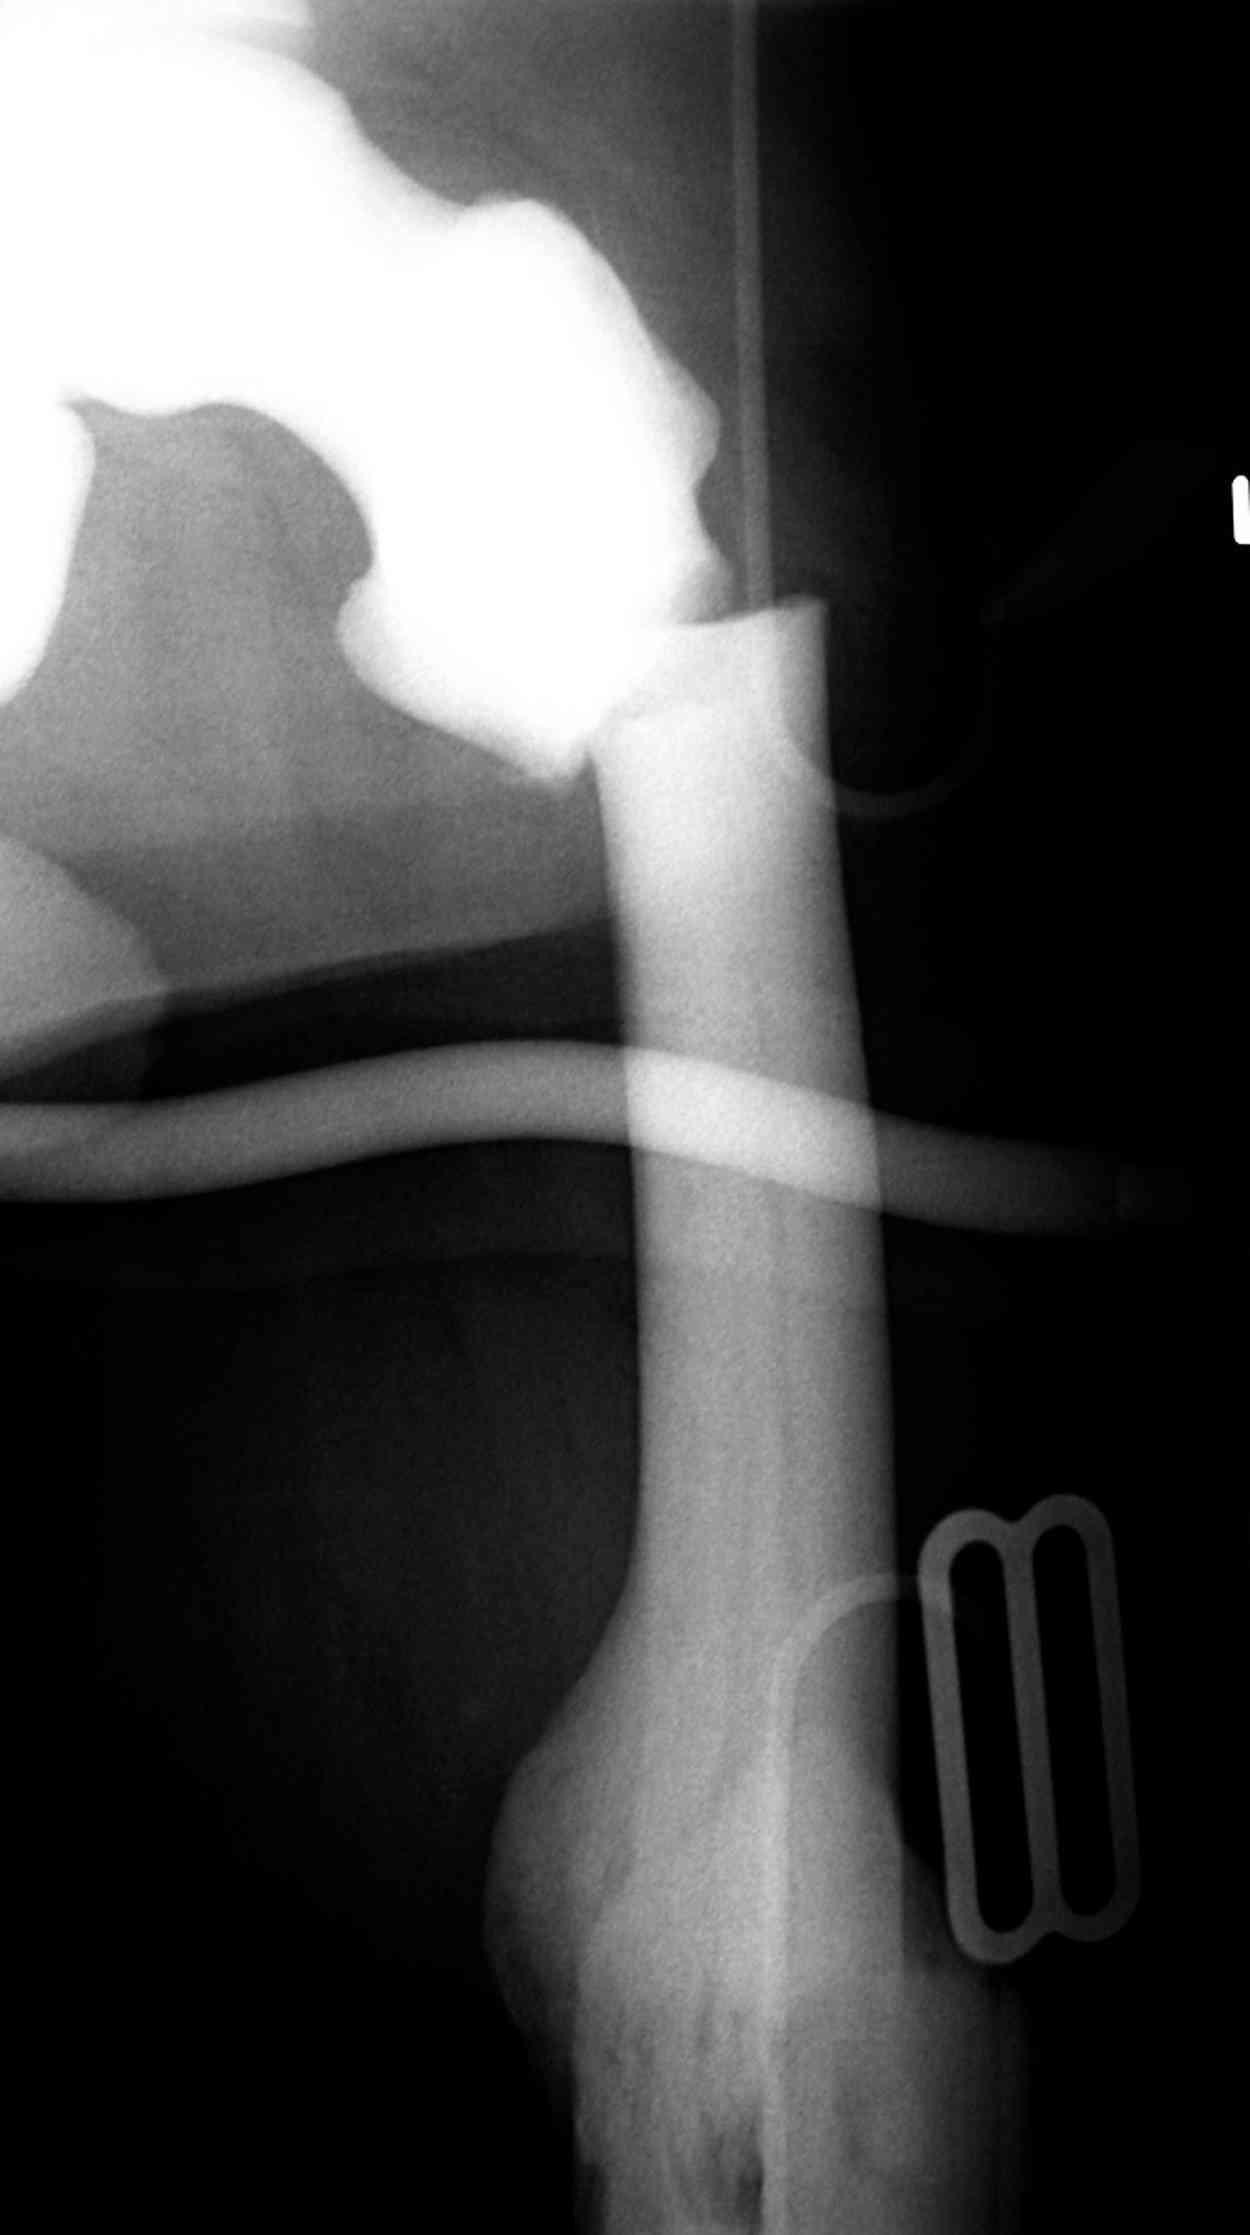

Re: [2/3] Перелом проксимального бедра

Здесь у меня дополнительные снимки с большим разрешением и в разных режимах, а то те дигитал снимки совсем очень блеклые, может, эти изображени изменят выбор тактики